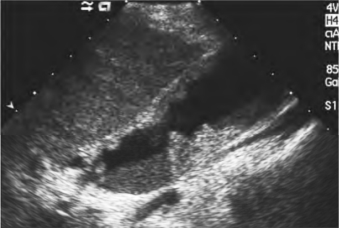

(1)厚壁型:胆囊壁呈局限性或弥漫性不均匀增厚,常以颈部或体部更为显著。回声分布不均匀,外壁不光滑,内壁粗糙,不规则(图25-10)。

图25-10 胆囊癌(厚壁型)声像图